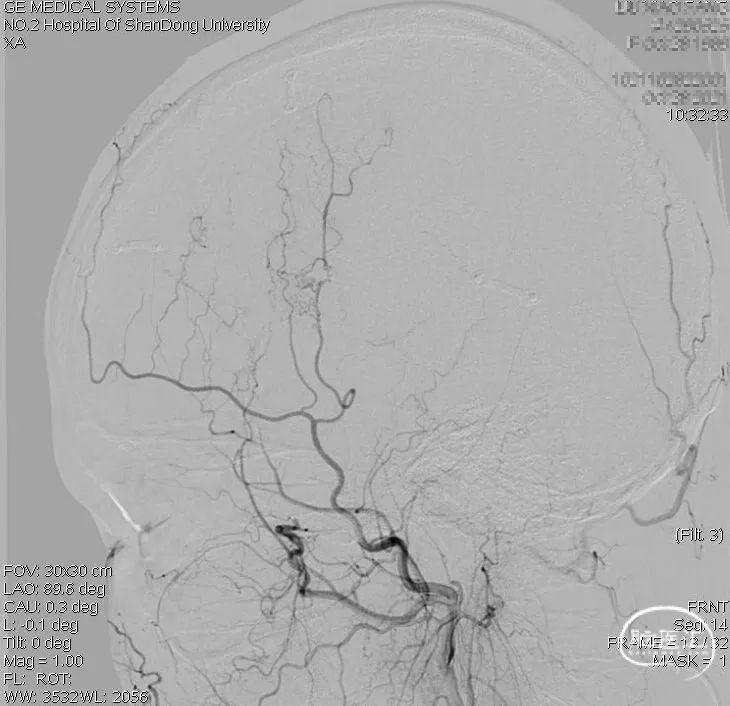

复查DSA:右侧颈外动脉侧位造影显示桥血管(右侧颞浅动脉顶支)走行向大脑半球上外侧面中央前回区域。

周围还可以看到一些颞浅动脉额支和硬膜新生血管供血。

做磁共振单支血管供血范围t-ASL检查,可以看到右侧颞浅动脉向中央前回区域供血。

如果标记右侧颈外动脉,脑内看到的标记区域包括颞浅动脉顶支(桥血管)和新生血管(颞浅动脉额支和脑膜新生血管)的供血范围;上图是仅仅标记颞浅动脉,所以主要是桥血管的供血区域,排除了新生血管的供血。

从DSA和t-ASL的结果来看,桥血管主要供应了中央前回,也就是运动中枢的范围,这符合我术前的设想。我的目的,就是先保证运动区的供血,防止运动区梗塞造成瘫痪等重要神经功能障碍。